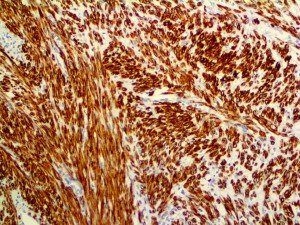

The first cytokines released are interleukin 1β (IL-1β) and tumor necrosis factor-α (TNF-α), which attract a variety of circulating white blood cells (WBCs) to the infection site, including neutrophils, monocytes, macrophages, and natural killer (NK) cells. This response, along with the antipathogenic chemicals released by these cells (i.e., complement), comprise the innate immune response. These cells directly attack the invading pathogen and also release additional cytokines, chief among them interleukin-1 and 6 (IL-6). IL-6 is essential for invoking the adaptive immune response, which calls T-cells, B-cells, and T helper (Th) cells to the infection site. IL-6 also stimulates further recruitment, proliferation and activation of macrophages.

It is the ICU physician who is most likely to witness one of the deadliest manifestations of the abnormal immunological response, the cytokine storm syndrome (CSS). This response is also referred to by some as the cytokine release syndrome (CRS). CSS is characterized by continuous activation and expansion of macrophage and lymphocyte populations, which secrete large amounts of cytokines, causing the cytokine storm. This massive cytokine release is akin to hemophagocytic lymphohistiocytosis (HLH) disease, a syndrome characterized by initial unchecked and persistent activation of cytotoxic T lymphocytes and NK cells.

This activation induces inflammatory monocytes to highly express IL-6, starting a localized and then systemic cascade effect that results in hyperproduction of IL-6, which accelerates the inflammatory process. Because IL-6 also increases vascular permeability, excessive levels cause blood vessels to become very leaky. This, along with clotting factors released from vascular endothelial cells, stimulates the coagulation cascade, resulting in microthrombosis (tiny clots), which leads to ischemia and tissue death of the kidney, intestines, heart, liver, brain and extremities.